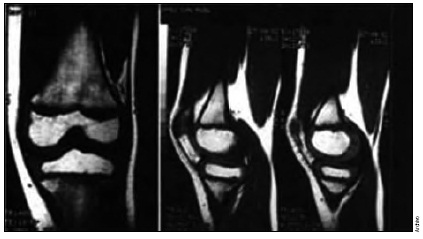

Con base en el cuadro clínico, exploración física y estudios de imagen (resonancia magnética nuclear), el demandado diagnosticó lesión meniscal, condromalacia tricompartimental y síndrome de hiperpresión lateral en rodilla izquierda; determinó la necesidad de artroscopía de rodilla izquierda, la cual se realizó el 6 de abril de 2011. La nota operatoria reportó realización de condroplastía patelar, troclear, condilar medial y lateral, sinovectomía, liberación retinacular lateral, sin complicaciones. Los diagnósticos postoperatorios fueron: condromalacia tricompartimental grado IV, síndrome de hiperpresión lateral, sinovitis en rodilla izquierda.

La gammagrafía ósea o la resonancia magnética nuclear, deben emplearse cuando aparece dolor brusco en el compartimiento interno de la rodilla, para descartar necrosis del cóndilo femoral interno, y en los estadios I y II, cuando se plantee realizar osteotomía y se requiera conocer la situación del compartimiento externo. La resonancia magnética nuclear es un apoyo para el diagnóstico; sin embargo, alteraciones degenerativas pueden ser confundidas con desgarros, y las alteraciones encontradas en la cirugía no se correlacionan de manera absoluta con las de imagen de resonancia magnética.

En la exploración física, el facultativo reportó: efusión de rodilla izquierda, dolor intenso a la palpación de la línea articular medial, extensión 0°, flexión 100°, McMurray medial positivo, cepillo positivo, fuerza muscular 4/5. La magnética nuclear confirmó el diagnóstico de lesión de menisco, refirió además, lesión del ligamento cruzado anterior. Por lo que explicó a la paciente el procedimiento de artroscopía de rodilla izquierda, el cual fue aceptado. En ese sentido, no se observan elementos de mala práctica que puedan atribuirse a la actuación médica del demandado, pues se acreditó que ante el cuadro clínico atendió las obligaciones de medios de diagnóstico y propuso el tratamiento correspondiente.

Durante el juicio, la actora (paciente) aportó informe de resonancia magnética de rodilla izquierda del 12 de febrero de 2011, el cual reportó: menisco medial con imagen sugestiva de ruptura en el cuerno posterior; imagen sugestiva de lesión grado I del ligamento colateral medial, pequeño aumento del líquido sinovial y cambios degenerativos en el cartílago articular en el cóndilo medial del fémur.

El informe del ortopedista que atendió de manera ulterior a la paciente, refiere que encontró dolor difuso y derrame articular, extrayendo 40 cm3 de líquido sinovial, por lo que indicó antiinflamatorio y reposo relativo, sin obtener evolución satisfactoria, razón por la cual, se efectuó resonancia magnética de rodilla que reportó: meniscopatía medial, cambios secundarios a cirugía, tendonitis de ligamento colateral medial, derrame articular y plica medial, fractura condral con defecto cartilaginoso en la faceta lateral de la rótula, lateralización patelar, explicando que si el dolor persistía, requeriría intervención de rodilla (artroscopía y medialización de rótula).